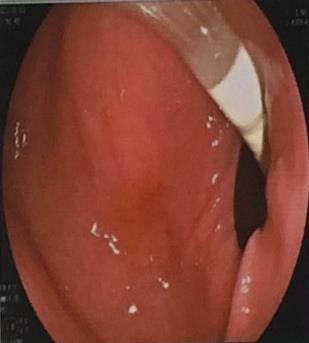

• 超声内镜引导下胃旁曲张静脉精准断流术治疗食管胃静脉曲张出血的疗效分析(附20例报告)

2025, 31(8):85-90. DOI: 10.12235/E20250036

摘要 (153) HTML (42) PDF 5.38 M (98) 评论 (0) 收藏

摘要:目的 探讨超声内镜引导下胃旁曲张静脉精准断流术治疗食管胃静脉曲张出血的疗效。方法 回顾性分析2024年1月1日-2024年12月31日于该院接受超声内镜引导下胃旁曲张静脉精准断流术治疗的20例肝硬化食管胃静脉曲张出血患者的临床资料,并评估治疗效果。结果 20例患者均顺利完成超声内镜引导下胃旁曲张静脉精准断流术;注射组织胶联合置入弹簧圈(16例)和单独注射组织胶(4例)均成功阻断胃旁来源的曲张静脉;所有患者均未发生穿孔、食管贲门狭窄、大出血、败血症和异位栓塞。1例单独注射组织胶的患者,术后胃旁曲张静脉少许渗血,经降低门静脉压力治疗3 d后好转,另1例单独注射组织胶患者,术后出现低热,抗感染3 d后体温恢复正常。结论 超声内镜引导下胃旁曲张静脉精准断流术治疗食管胃静脉曲张出血的临床疗效好,异位栓塞、大出血、感染和穿孔等并发症少,但仍需要密切随访,观察胃旁曲张静脉的排胶问题。